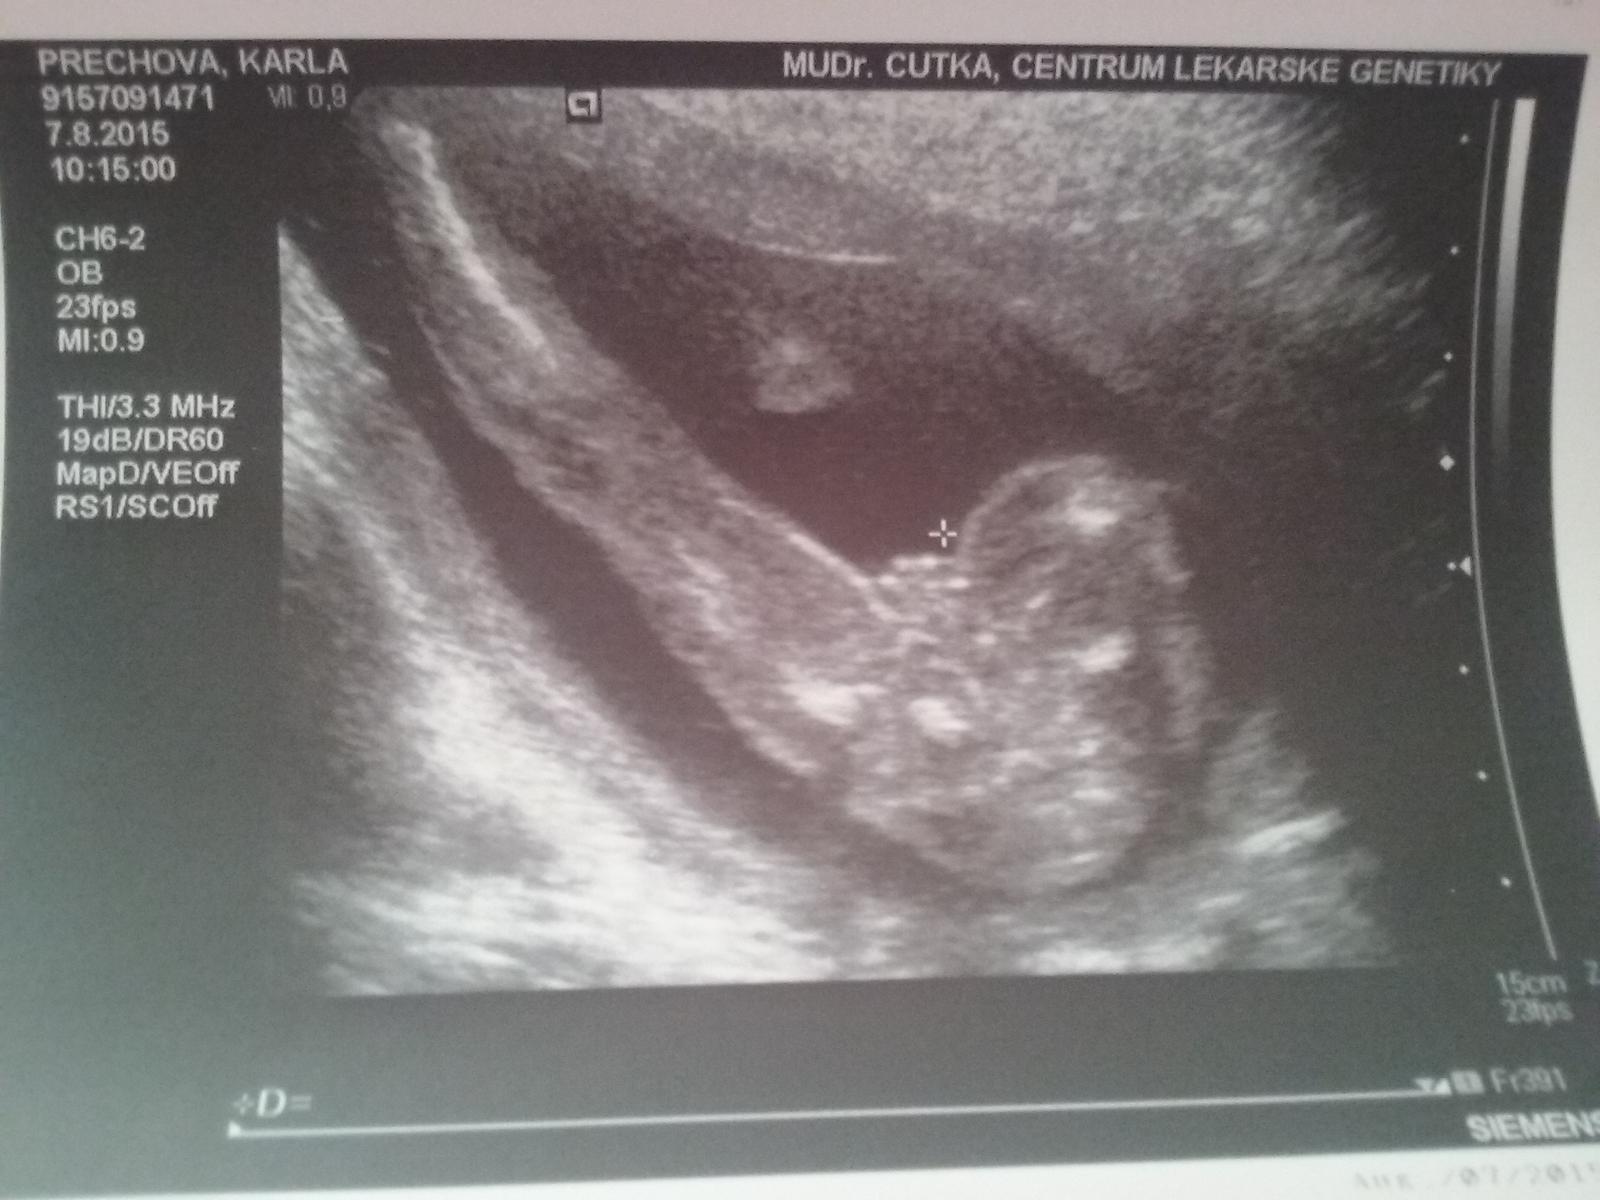

Zajímá mě váš názor. Kluk či holka?

Je to genetika 20tt a dr rekl ze jasna holka ale me to porad prijde sporne

Ja bych rekla, ze holčička ma tam buchtu.. U nas nam buchtu ukazoval, tak vim jak vypada. Cekame dvojčatka parecek

@karla12345 Já myslim, že holčička.Já mám syna a dceru a fotky u obou totožné s tou tvou a u syna byl teda videt pytlik pekne...Sofinka(dcerka) vypadala stejne jako tvoje fotka